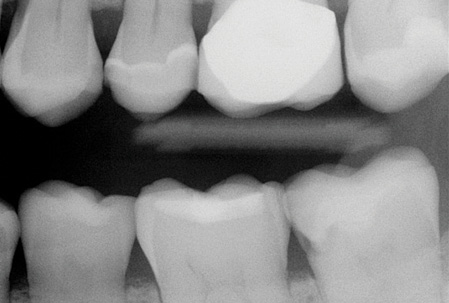

Your observations are shared by the majority of mature practitioners. Many younger practitioners have not noticed the inadequacy of periapical and bitewing radiographs because they do not have a historical perspective relative to the problem you described. I recently received a typical example from an excellent general practitioner in the eastern part of the US (figures 1 and 2).

Upon initial examination of the radiograph, only a few minor lesions were observed. When the dentist excavated the caries in the maxillary second molar, the extreme depth of the lesion was able to be seen. This is not an abnormal finding. In spite of the ability to manipulate digital images through magnification, coloring, texturing, and change of contrast, most small lesions and some large lesions are often missed.

Figure 1: Note the lack of any clearly identifiable presence of deep carious lesions on this current-generation digital radiograph.